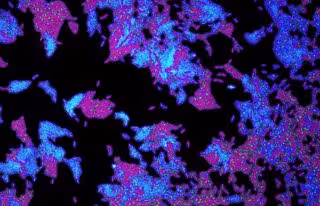

Archivo - Células de la bacteria patógena 'Pseudomonas aeruginosa'.

Archivo - Células de la bacteria patógena 'Pseudomonas aeruginosa'. - SEAN BOOTH - Archivo